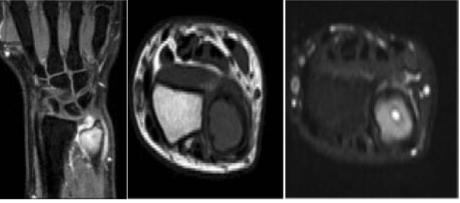

A 16-year-old male came to the Outpatient department with pain and swelling in the left wrist since 3 days. He gave a history of fall while playing football 3 days back. On Examination, there was presence of swelling on the dorsal ulnar aspect of the wrist of size 2.5 cm. Range of movements of the wrist was assessed and was found to be 70 degrees of flexion, 45 degrees of extension, 15 degrees of radial deviation and 10 degrees of ulnar deviation. Circumduction, pronation, and supination were restricted and painful. Radiograph of the left wrist was taken. There was no evidence of fracture on the radiograph, however an osteolytic lesion inducing an expansion was seen in the meta-epiphyseal region of the ulna [Figure 1]. A Magnetic resonance imaging examination was performed. It showed in the T1 sequence presence of a hypointense signal and in the short T1 inversion recovery (STIR) sequences a hyperintense signal was seen which showed enhancement after contrast administration [Figure 2].

Figure 2: MRI of the Left Wrist showing hypointense signal in the T1 sequences and a hyperintense signal in the short TI inversion recovery (STIR) sequences.